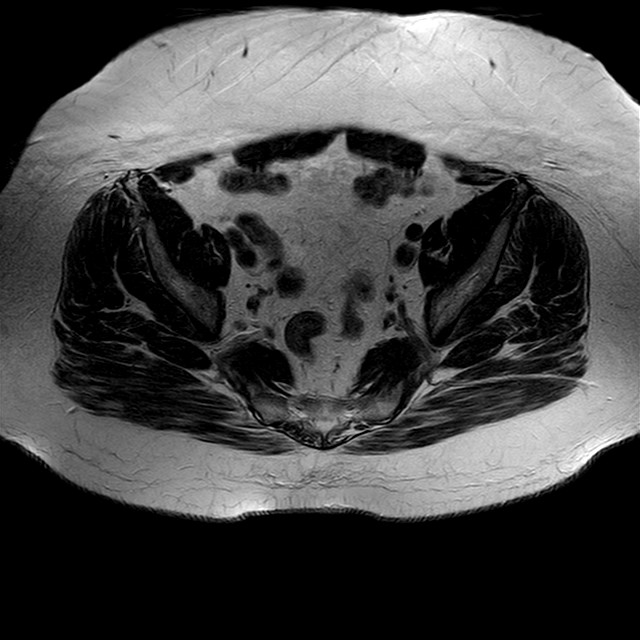

Esami: RMN BACINO

eT2w TSE

Evidenti e simmetriche alterazioni osteofitosiche in regione coxo femorale con riduzione delle rime articolari. Degenerazione completa del cercine glenoideo. Non attuali segni di versamento articolare. Non segni di edema osseo che escludono attuale algodistrofia od osteonecrosi. Lieve e simmetrica riduzione del trofismo della muscolatura glutea.